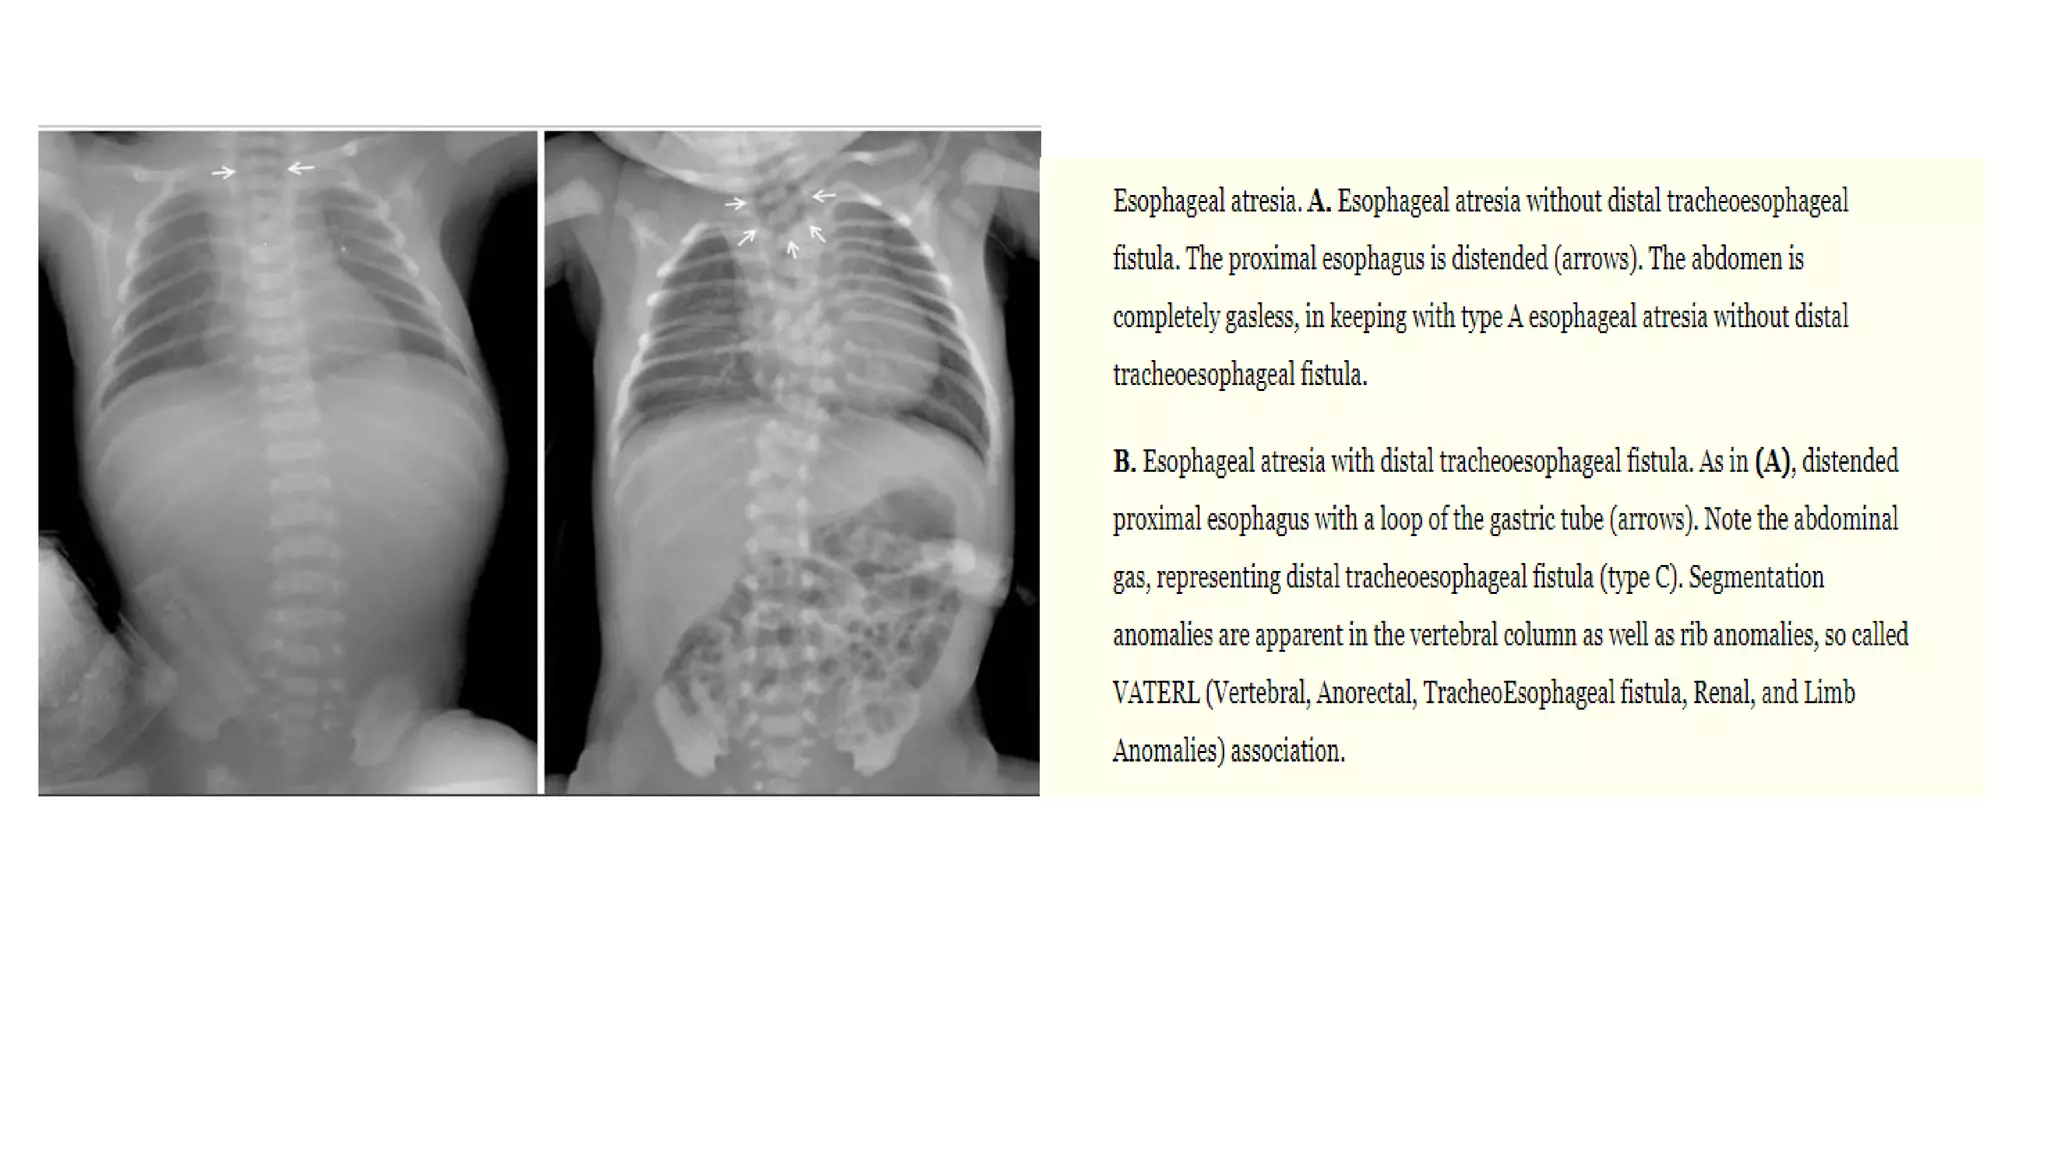

This document provides an overview of neonatal chest x-rays, including when they should and should not be performed, what a normal x-ray looks like, common positions of tubes and catheters, and common causes of respiratory distress in neonates. It discusses the appearance of a normal chest x-ray as well as conditions like respiratory distress syndrome, transient tachypnea of the newborn, meconium aspiration syndrome, and pneumonia. Surgical conditions like diaphragmatic hernia and esophageal atresia are also reviewed.